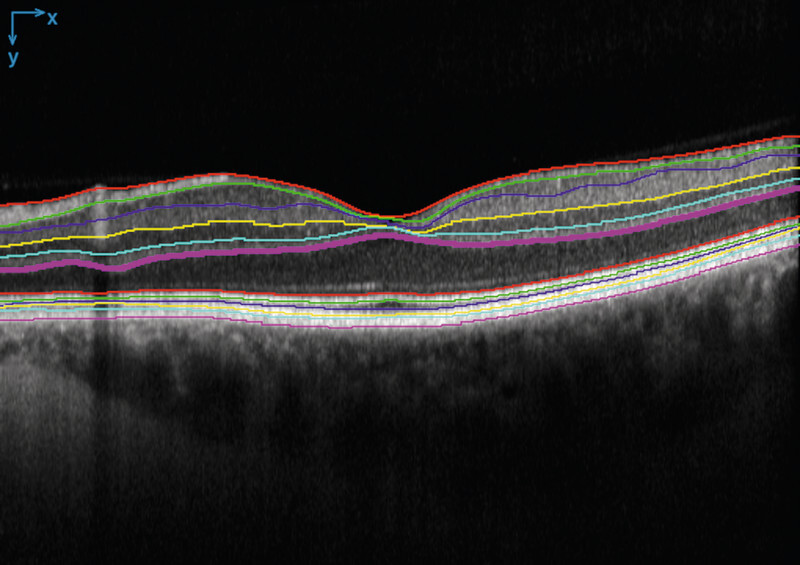

背景:在遗传性视网膜疾病(IRDs)患者的光学相干断层扫描(OCT)扫描中,核外层(ONL)厚度的测量已被公认为是感光细胞保存的替代标记。目前的自动分割工具无法对IRD进行OCT分割,而手动分割又非常耗时:本研究筛选了具有可用 OCT 扫描的 IRD 患者。此外,还包括无视网膜疾病患者的 OCT 扫描,以便为人工智能(AI)提供训练数据。我们在健康患者身上训练了一个基于 U-net 的模型,并对 IRD 患者的扫描应用了领域适应技术:结果:我们建立了一种基于人工智能的图像分割算法,它能可靠地分割 IRD 患者 OCT 扫描中的 ONL。在测试数据集中,该算法的骰子得分率为98.7%。此外,我们还为每位患者生成了全视网膜厚度图和 ONL 层厚度图:结论:准确分割 OCT 扫描图像上的解剖层对于建立视网膜结构与视觉功能相关联的预测模型至关重要。我们的 OCT 图像分割算法可为进一步研究 IRD 提供基础。

Results: We established an AI-based image segmentation algorithm that reliably segments the ONL in OCT scans of IRD patients. In a test dataset, the dice score of the algorithm was 98.7%. Furthermore, we generated thickness maps of the full retinal thickness and the ONL layer for each patient.